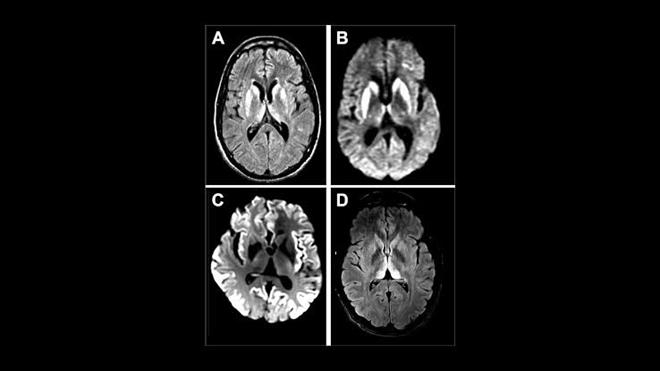

ئەم تێکچوونە کوشندەیە بەهۆی جۆرە پرۆتینێکی نائاساییەوە دروست دەبێت کە پێیان دەوترێت "پڕایۆن". ئەم پڕایۆنانە دەبنە هۆی تێکشکاندنی شانەکانی مێشک و دروستکردنی کوناوی ورد و بچووک تێیدا، بە جۆرێک مێشک لە ژێر مایکرۆسکۆپدا وەک ئیسفەنجێک دەردەکەوێت. نیشانەکانی نەخۆشییەکە بریتین لە لەدەستدانی خێرای یادگە، گۆڕانی کەسایەتی، تێکچوونی هاوسەنگی جەستە و داڕمانی توندی توانای عەقڵی، کە وای لە مرۆڤ دەکات لە ماوەیەکی زۆر کورتدا توانای ناسینەوەی دەوروبەری نەمێنێت.